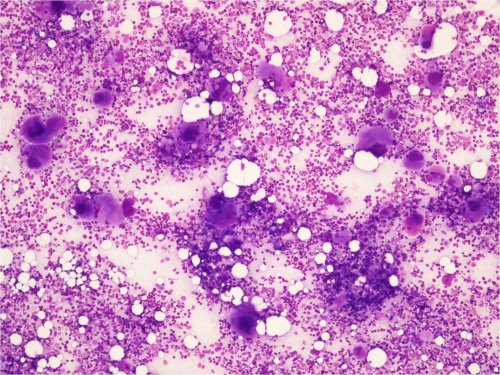

Akuutti ITP

• Yleinen lapsilla

• Perifeerisessä veressä trombosytopenia, joka joskus hyvinkin vaikea (B-Trom jopa < 5)

• Luuytimen megakaryosyyttien määrä lisääntynyt

• Megakaryosyyttien nuoruusmuotoja esiintyy, samoin pienikokoisia muotoja

• Trombopoieesin turnover lisääntynyt

• Kyseessä trombosyyttien immunologinen kato

• Muut solulinjat normaalit

Kuva 20. Akuutti ITP 2 kk:n ikäisellä vauvalla. Luuytimen yleiskuva. Erittäin runsaasti megakaryosyyttejä.

Kuva 21. Akuutti ITP, luuytimen yleiskuva. Runsas megakaryosyyttien määrä yhdessä perifeerisen trombosytopenian kanssa sopii akuuttiin ITP:hen. 2 kk:n ikäinen vauva.